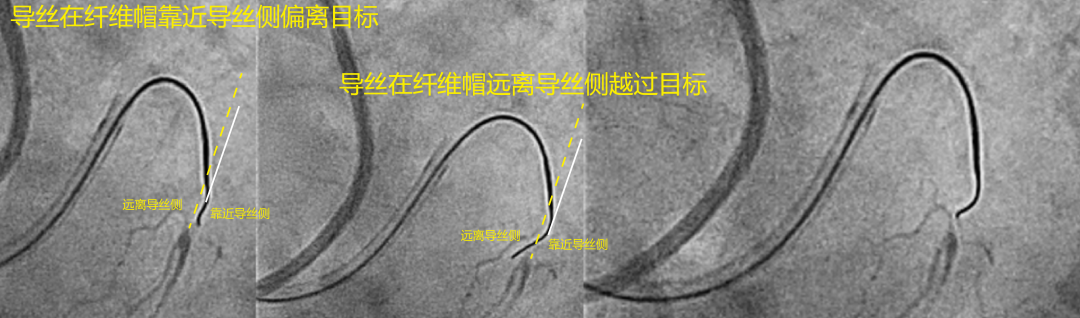

即使导丝头端被精确旋转指向远端纤维帽,导丝头端仍可能穿刺失败:近侧偏离或远侧偏离。近侧偏离是指导丝向前移动过远而没有横向移动的情况下,导致导丝在靠近导丝侧错过目标。解决近侧偏离的方法是允许导丝有更远的行进距离,以便它有足够的横向移动刺向目标。为此,必须在不旋转的情况下将导丝拉回到更近端的位置,并再次向前穿刺(见图3)。另一种穿刺失败是远侧偏离。在远侧偏离中,导丝横向移动过多,在到达远端纤维帽水平之前就错过了目标,在远离导丝侧越过CTO目标(见图4)。在这种情况下,解决方法是将导丝拉回,直到导丝头端刚好位于远端纤维帽水平上方,然后旋转导丝180°,使导丝头端指向远端纤维帽目标,并向前穿刺。

图4 近侧偏离与远侧偏离

左侧:1) 开始导丝操作;2) 导丝在靠近导丝侧错过了CTO目标;3) 解决近侧偏离的方法是将导丝向近端撤回,为导丝横向移动留出距离;4) 然后导丝就能刺向目标。右侧:1) 开始导丝操作;2) 导丝在远离导丝侧越过CTO目标;3) 解决远侧偏离的方法是将导丝拉回至目标附近;4) 旋转导丝180°;5) 重新穿刺命中目标。